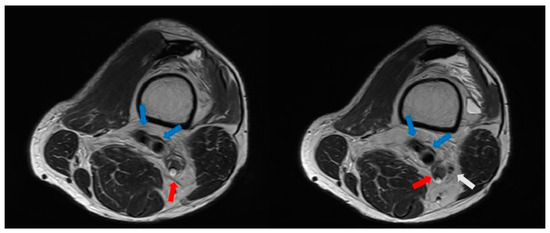

2.1. Preoperative Evaluation